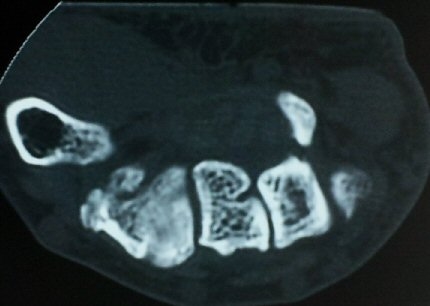

¼ÒÁö±¸ ³»Ãø¿¡ ȾÀ¸·Î ŽÃËÀÚ¸¦ ´ë¾î °¥°í¸®»À °¥°í¸® ³»Ãø¸é ÇÇÁú°ñÀ» °üÂûÇÏ´Ï(¾Æ·¡ ±×¸²)

°¥°í¸® ÇÇÁú°ñ ¿¬¼Ó¼º ¼Ò½Ç(loss of cortical continuity of hook of hamate)ÀÌ °üÂûµÈ´Ù(±×¸² 1, 2).

ÇÇÁú°ñ ¿¬¼Ó¼º ¼Ò½ÇÀº °ÇÃø°ú ºñ±³ÇØ¸é ´õ¿í ¶Ñ·ÈÇÏ´Ù(±×¸² 3, 4).

ÄÄÇ»ÅÍ ÃÔ¿µ»ó °¥°í¸®»À °¥°í¸® °ñÀýÀ» º¸ÀÓ(±×¸² 5, 6, 7).